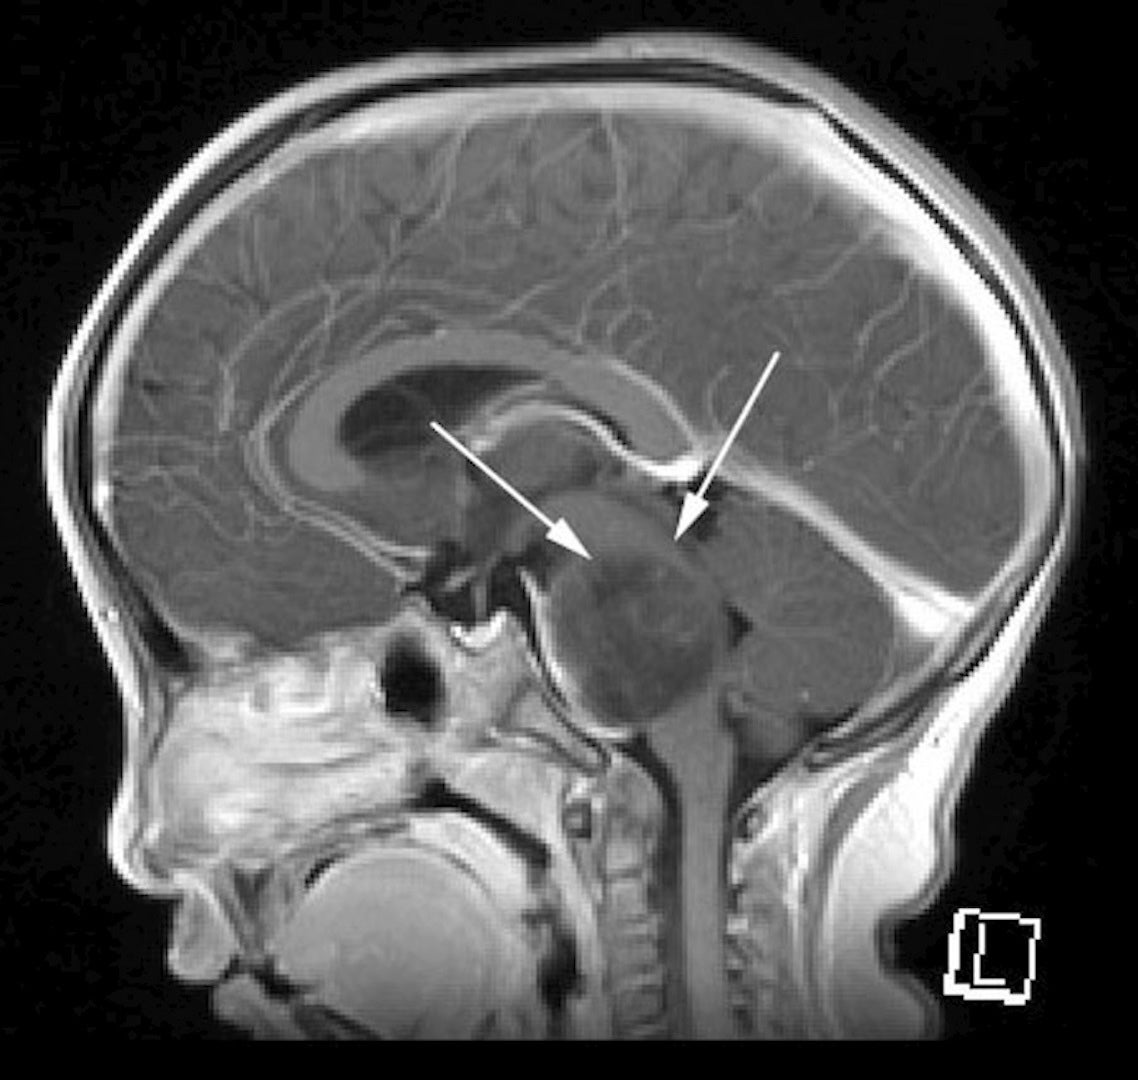

今回のフォーラムで取り上げる中心的な疾患は、DMGのカテゴリーの中でも、より難治性の高い「びまん性内在性橋グリオーマ」‥‥Diffuse Intrinsic Pontine Glioma(略称:DIPG)と称されるものです(図2)。これは、脳幹部の「橋」と言われる部位(図1)に悪性腫瘍が発生する病気で、年間約50名前後の子どもたちが発症します。生命活動にとって重要な神経が交差する場所に発生したがんは、中枢神経を毀損し、身体をまひさせ、その自由を奪っていきます。重要な神経が通る部位のため、そこにメスを入れての摘出手術は不可能であり、また、現時点では確定的な治療薬も見つかっていません。わずかに放射線治療により、一時的な寛解期が訪れますが、約半年以内で再発し、その後の治療法は無く、呼吸や血圧を維持できなくなり、やがてほぼ100%の確率で死に至ります。発症から1年以内に亡くなる確率は50%以上という、最も過酷な小児がんです。現在まで、世界中でこの病気の治療法が探索されて来ましたが、未だ形にはなっていません。しかし、近年、遺伝子解析技術の飛躍的発展によって、徐々に有効と思われる治療法が見つかりつつあります。

図1 脳の各部位

図2 DIPGのMRI画像